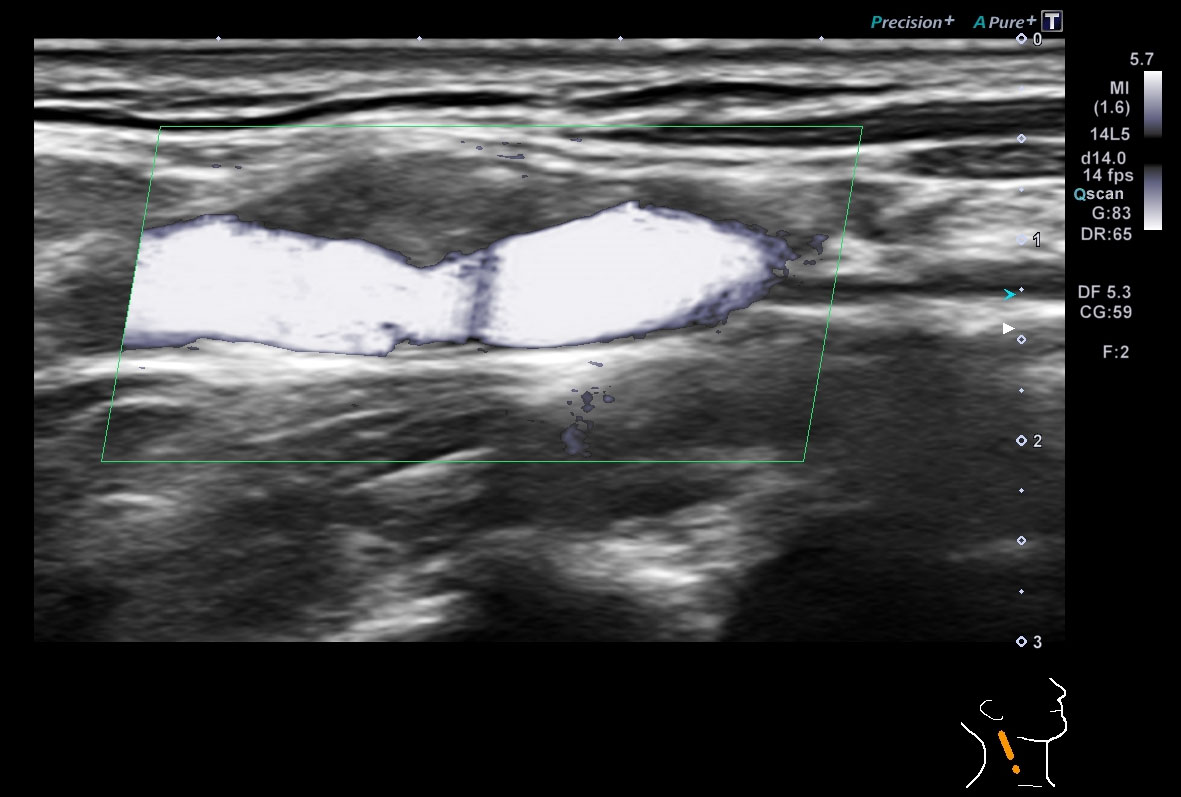

超音波(エコー)

下記など多くの診断ができます。

各項目をクリックすると診断画像が表示されます

超音波(エコー) 診断画像

- 内頸動脈狭窄

- 静脈瘤